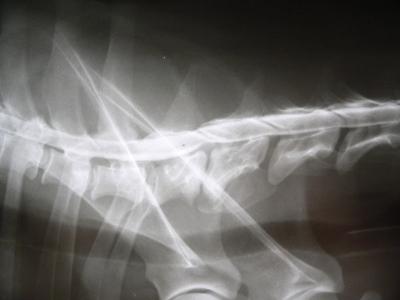

Provádíme operace páteře a hrudníku, wobbler, SLOT, totální endoprotézy, prasklé kolenní vazy, LCC, TPLO, TTA, dysplasie, TPO, trojité osteotomie pánve, JPS, diagnostiku kulhání, kožní onemocnění, perineální kýly, osteosyntézy, OCD. K dispozici máme vybavení jako RTG, USG, krevní analyzátory, atp.